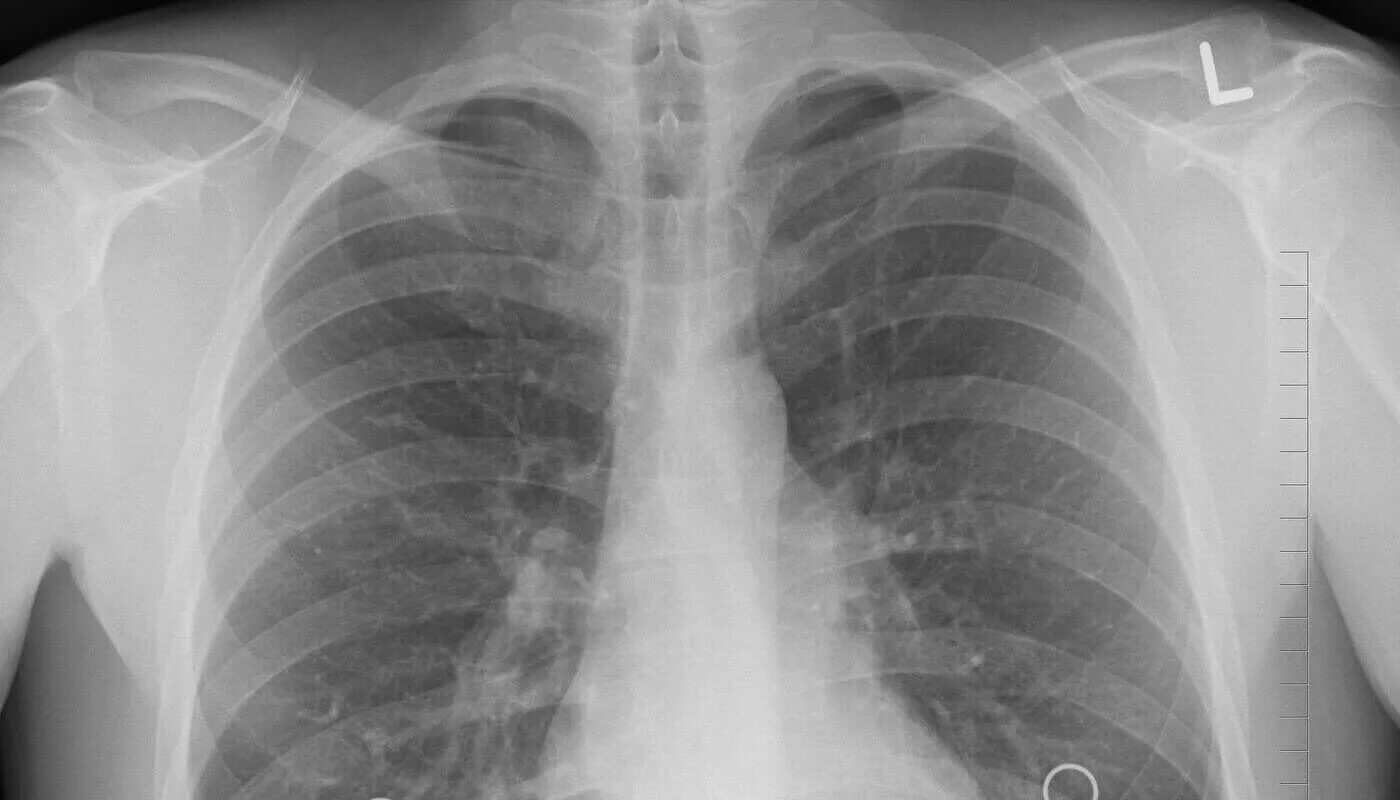

Почему в легких